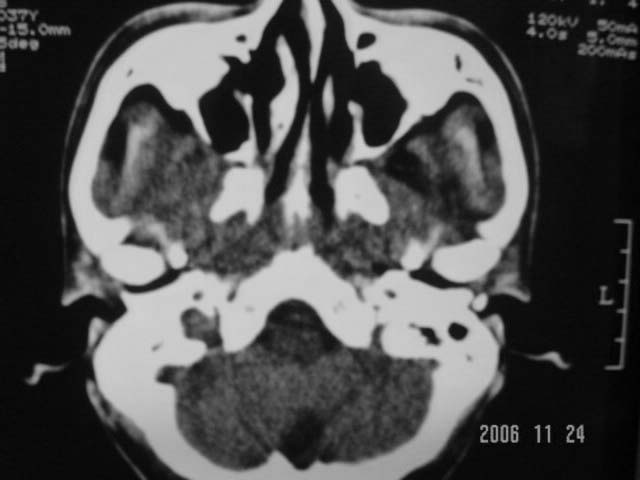

右侧鼻咽部软组织肿块,颅底骨质破坏,右侧颈部淋巴结肿大;诊断:鼻咽ca、右颈部淋巴结转移、颅底侵犯

右侧鼻咽侧后壁不规则增厚,咽隐窝变钝,咽旁间隙变狭窄,见组织结节影[哨兵征],蝶骨似破坏,蝶窦内充塞软组织影,翼内外肌上分间隙模糊,右颈后三角区淋巴结肿大,右侧乳突增高气房消失。考虑鼻咽癌伴蝶窦侵犯及淋巴结转移,右侧浆液性中耳炎。其他恶性病变待排。

右侧鼻咽癌伴同侧颈部淋巴结转移可能性大.要是有骨窗,能看到更多征象,有助于诊断

鼻咽癌伴右颈部淋巴结肿大,典型